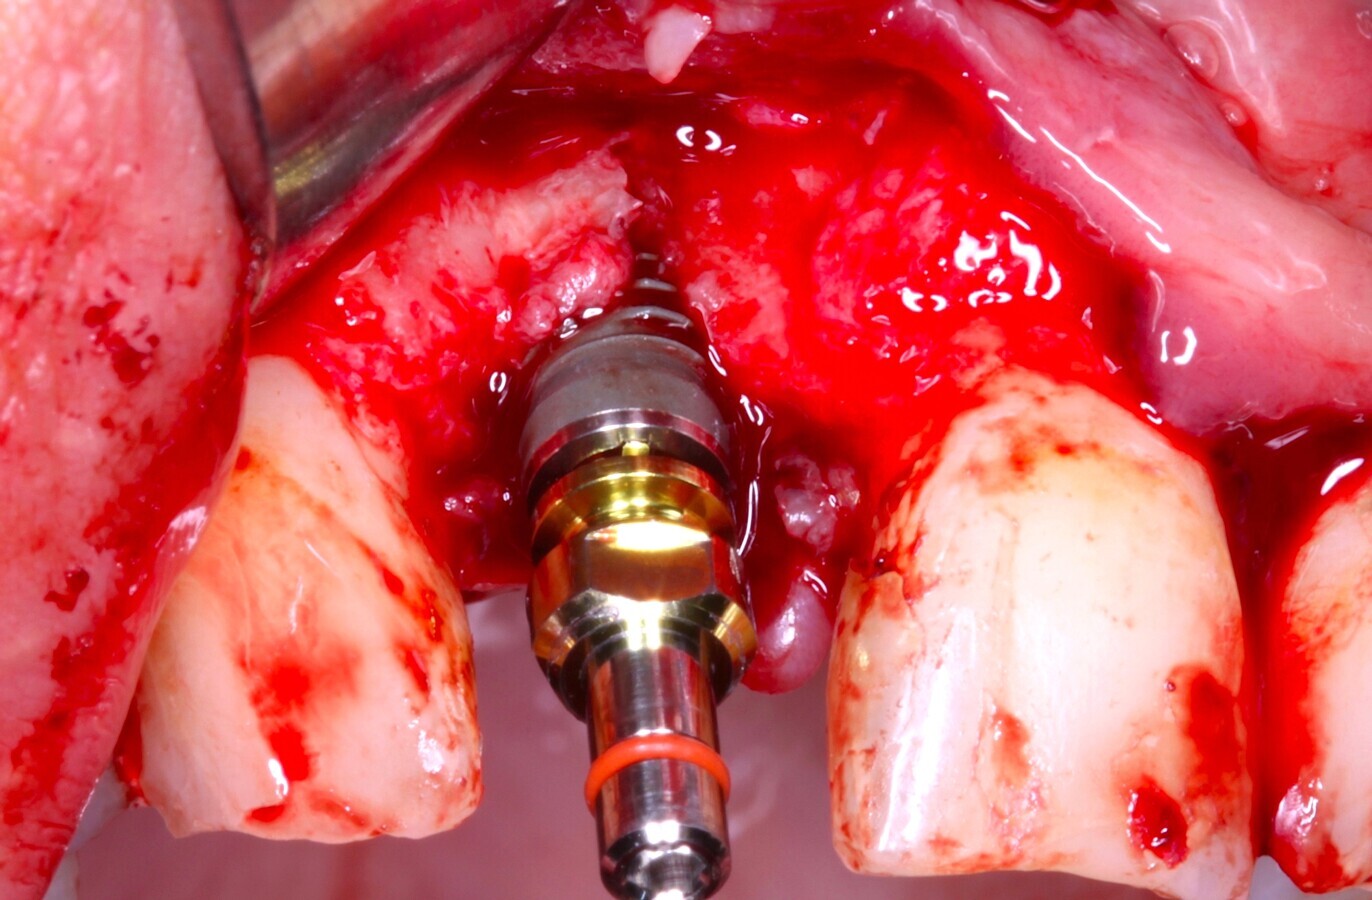

Fig. 32 Figura 32

7. Inserción del implante seleccionado.

8. Reposición del colgajo mucoperióstico, en caso necesario liberación del periostio para garantizar un colgajo sin tensión, el cierre primario de todo el lecho10.

9. Sutura del colgajo con puntos simples con sutura 4/011,12.